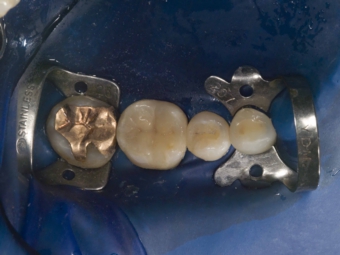

ラバーダム防湿

歯にラバー(ゴムの一種)で出来たマスクのようなものを装着し、唾液等による汚染から隔離します

マイクロスコープ

根管治療にはマイクロスコープは必須です

狭くて暗い根管の中を適切に清掃し、感染の除去を行う場合、20倍以上に拡大して観察が出来、診ている術者の視線の軸と光の軸が一致し、完全に見えるのがマイクロスコープです。